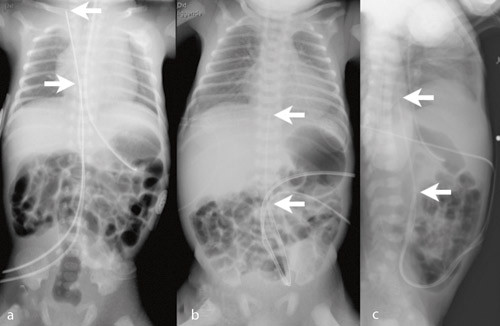

278 navlevenekatetre og 99 navlearteriekatetre ble innlagt hos totalt 298 nyfødte. 78 (26 %) fikk både arterie- og venekateter. Figur 1 – 3 viser røntgenbilder med ulike kateterposisjoner. I ett tilfelle fikk pasienten utilsiktet to navlevenekatetre (fig 2a) og i to tilfeller fant begge katetrene veien til samme navlearterie (fig 2b og 2c). Indikasjonene for innleggelse var prematuritet hos 156 (52 %), asfyksi hos 41 (14 %), infeksjon hos 37 (12 %), respirasjonsbesvær hos 24 (8 %), misdannelser hos 12 (4 %) og andre indikasjoner hos 28 (9 %).

Tabell 1 angir kateterposisjonene. Av navlearteriekatetrene var 45/99 (45 %) primært riktig plassert, og 77/278 (28 %) av venekatetrene. Navlearteriekatetre lå oftere for lavt (44/99; 44 %) enn for høyt (10/99; 10 %) (p < 0,001). Tilsvarende lå flere navlevenekatetre for lavt (126/278; 45 %) enn for høyt (75/278; 27 %) (p < 0,001). Hos 14 (5 %) av venekatetrene og seks (6 %) av arteriekatetrene var det krøll på kateteret (fig 3). For venekatetrene lå krøllen hos 11 i ductus venosus og hos tre i portveneområdet. For arteriekatetrene lå krøllen hos alle i aorta.